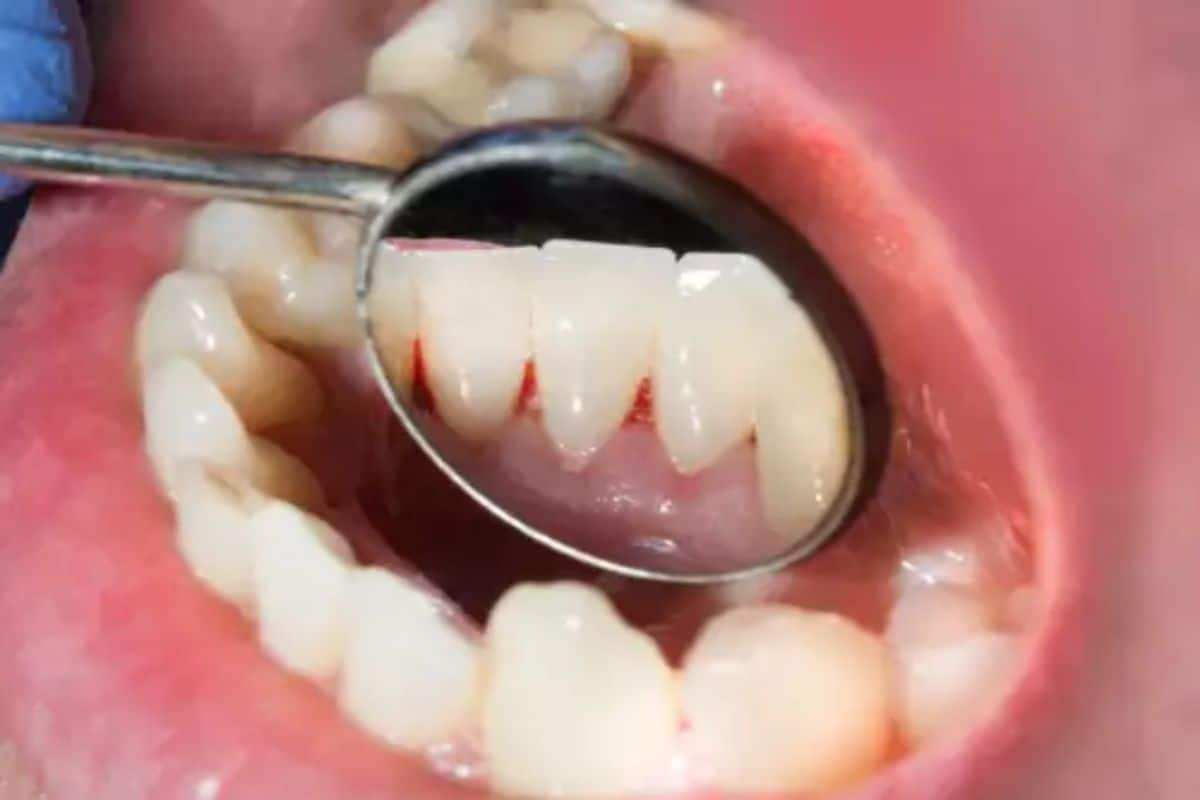

মুখে সাদা দাগ

মুখের ভিতরে সাদা কিংবা কখনও কখনও লাল দাগ ক্যানসারের ইঙ্গিতবাহক হতে পারে। যদিও এর পিছনে গ্যাসট্রিক সমস্যা কিংবা মুখের সংক্রমণের মতো বিভিন্ন কারণও থাকতে পারে। কিন্তু যদি এটি স্বাদ কিংবা কথাবার্তাকে প্রভাবিত করে তাহলে চিকিৎসকের পরামর্শ নেওয়া উচিত।